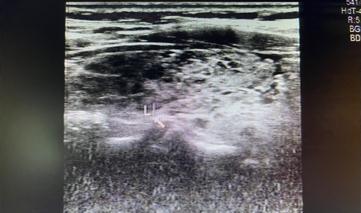

桥本氏甲状腺炎:甲状腺大小可正常,也可以呈非均匀性肿大,不过在疾病后期一般都表现为甲状腺缩小。超声图像一般分为弥漫型、局限型和结节形成型。其中结节形成型有时候经常会在体检时发现为结节而来就诊,有时候较难与恶性结节相鉴别,可以定期复查,或者超声造影或者进行结节穿刺进行进一步检查。

毒性弥漫性甲状腺肿(Graves病):大多为均匀性肿大,也有表现为非均匀性肿大的(较少),通常表现为腺体弥漫性低回声。很多患者就因为发现脖子肿大来就诊。毒性弥漫性甲状腺肿最典型的超声表现为“火海征”,即甲状腺的血供异常丰富,甲状腺上动脉通常都有增宽,一般超过2mm,流速增快。